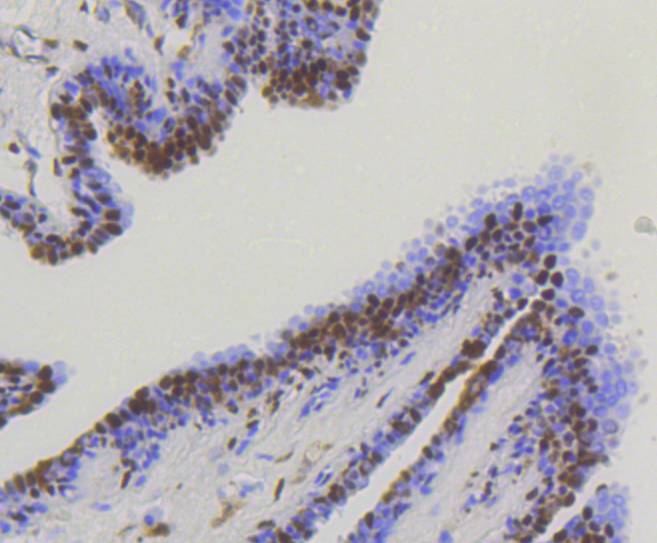

Immunohistochemical analysis of paraffin-embedded human colon cancer tissue using anti-YAP1 antibody. Counter stained with hematoxylin.

Immunohistochemical analysis of paraffin-embedded human kidney tissue using anti-YAP1 antibody. Counter stained with hematoxylin.